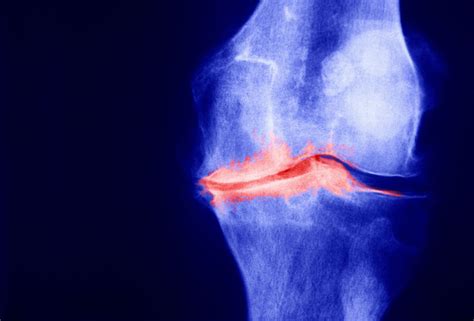

Diagnosis of Tricompartmental Degenerative Arthrosis

Diagnosing tricompartmental degenerative arthrosis involves a combination of medical history, physical examination, and diagnostic tests. The diagnostic process typically includes:

• Imaging Tests: X-rays, MRI, or CT scans may be ordered to visualize the joint and assess the extent of cartilage damage.